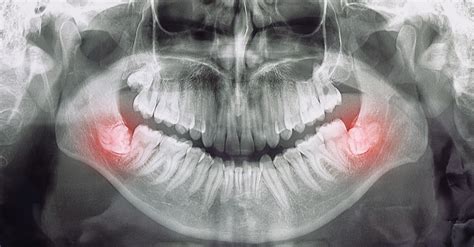

- Cordales retenidos: estos están completamente ocultos dentro de la encía. Las muelas del juicio ocultas pueden causar dolor, producido por infecciones, que dañan las raíces o los huesos de dientes contiguos. Además, pueden generar quistes o tumores de forma excepcional.

Extracción de las muelas del juicio e Impress

Si estás pensando en mejorar tu sonrisa y quieres saber si te han salido las muelas del juicio o si te van a salir, en Impress podemos ayudarte. Te haremos radiografías y las pruebas necesarias para ver el estado de tus molares y haremos una valoración sobre tus necesidades antes de iniciar el tratamiento de ortodoncia.

Muelas del juicio retenidas

Ya que no todos las dentaduras tienen el mismo tamaño y las mismas características, también existe la posibilidad de que las muelas del juicio se queden retenidas. Esto ocurre cuando en la boca no existe suficiente espacio para que crezcan de forma normal, de manera que crecen dentro de la encía y generar diversos problemas muy dolorosos.

La solución de las muelas del juicio retenidas suele ser sacarlas mediante cirugía oral o maxilofacial, aunque esto se realiza solamente cuando están ocasionando molestia en los demás dientes, en la encía e, inclusive, dolores de cabeza o migrañas, al ejercer presión en los nervios.